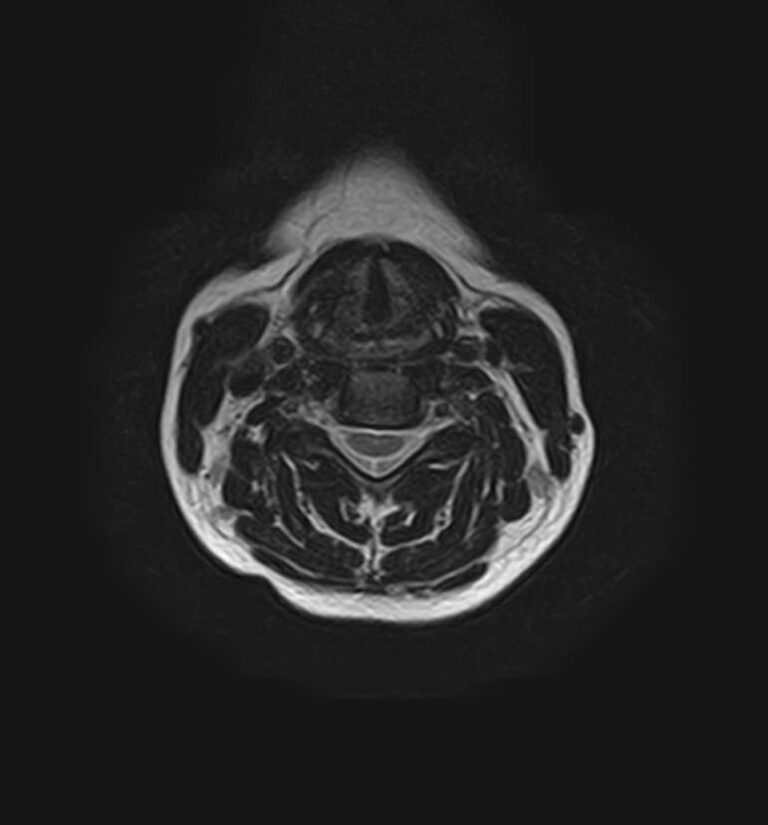

МРТ шейного отдела позвоночника позволяет проводить диагностику дегенеративных заболеваний позвоночного столба (в том числе межпозвонковых грыж, протрузий, остеохондроза), выявлять воспалительные, травматические изменения и объемные образования в области шейных позвонков и спинного мозга.

МРТ шейного отдела позвоночника позволяет выявить практически любые изменения в костных и мягких тканях. Исследование характеризуется высокой результативностью при следующих нарушениях:

• демиелинизирующие заболевания;